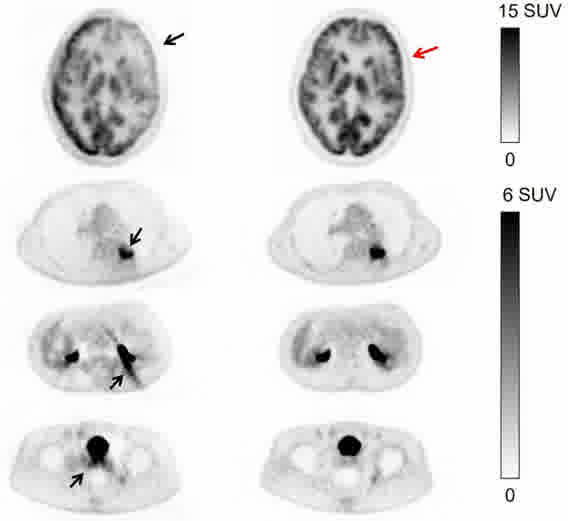

超低计数68Ga三符合重建

采用单事件、低能量事件等全流程数据进行全数字PET图像重建,解决低剂量、多核素等场景下高质量成像问题。

传统算法 改进的算法 双符合重建68Ga和18F混合的信号 三符合重建仅含68Ga的信号 传统算法 改进的算法 缺角度系统